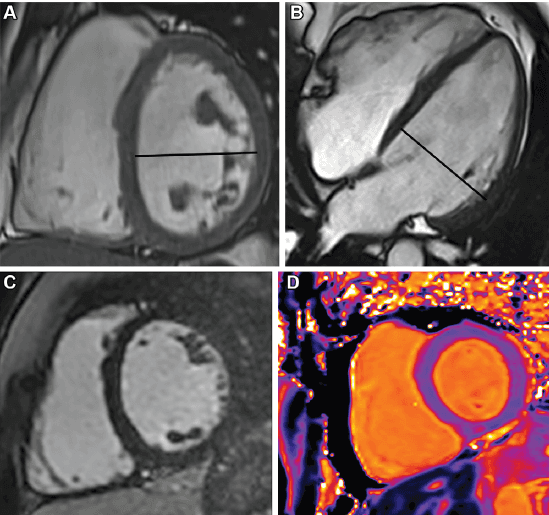

En el atleta, la RM es la herramienta más robusta para distinguir adaptación fisiológica de miocardiopatía o inflamación. Permite evaluar grosor parietal, relación masa-volumen, función biventricular, edema, fibrosis y cicatriz. En el remodelado fisiológico, la hipertrofia suele ser concéntrica, típicamente menor de 16 mm, con proporcionalidad estructural, ausencia de LGE y valores tisulares conservados. En cambio, la presencia de LGE, edema o alteraciones segmentarias obliga a abandonar la etiqueta de “corazón de atleta” como explicación automática. Incluso en zonas grises, la proporcionalidad importa más que el grosor aislado.

El gran reto no es detectar un corazón grande, un ventrículo dilatado o una pared engrosada. El reto es interpretar si ese hallazgo está en armonía con el tipo de entrenamiento, la función ventricular y la caracterización tisular. El paper es consistente en este punto: el remodelado inducido por ejercicio se reconoce por la proporcionalidad. La hipertrofia adaptativa suele ser concéntrica y menor de 16 mm. La dilatación fisiológica puede acompañarse de fracción de expulsión normal o levemente reducida, pero con respuesta funcional conservada y sin fibrosis significativa. La dilatación del ventrículo derecho, cuando es fisiológica, es global, no segmentaria, y sin alteraciones mayores de la motilidad regional.

Dos escenarios del paper concentran el mayor valor narrativo del blog. Primero, la miocarditis: la combinación de LGE subepicárdico o mesomiocárdico con elevación de T1 y T2 cumple criterios de Lake Louise y redefine temporalidad, riesgo y retorno al deporte. Segundo, las anomalías coronarias: el origen anómalo con trayecto interarterial e intramural puede ser silente en reposo, pero volverse crítico durante el ejercicio. El artículo subraya que estas anomalías se asocian con un riesgo 79 veces mayor de arritmia con el esfuerzo. Esa es la diferencia entre una imagen interesante y una imagen clínicamente decisiva.